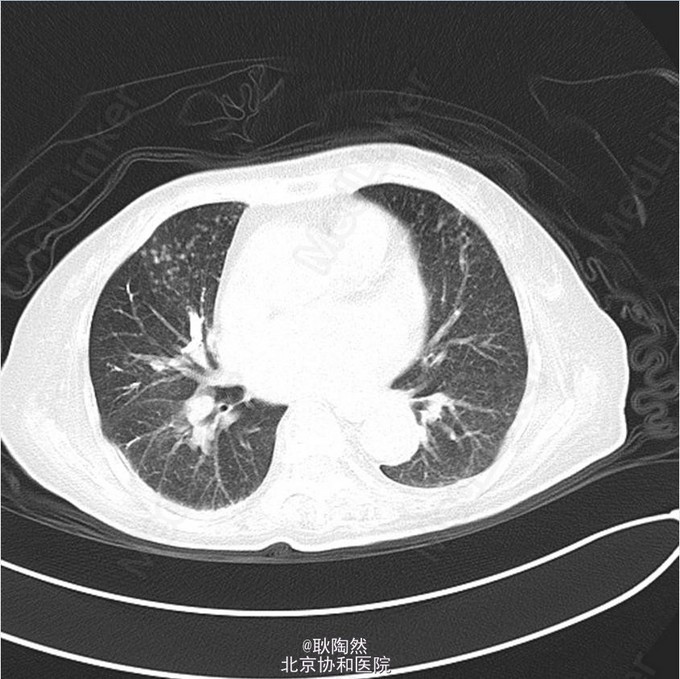

患者75岁老年女性,因“间断发热1年余,乏力、少语2周”于2014-12-25入院治疗。 2013年起患者无明显诱因出现发热,每日午后温度渐高,Tmax39℃,次日凌晨可降至正常。伴乏力,无盗汗、畏寒寒战、咳嗽咳痰等表现。外院胸部CT提示“肺部感染”,予莫西沙星治疗后体温正常。 2013-3患者出现T12椎体骨折,行手术治疗,术前有发热表现,予莫西沙星抗感染治疗后体温正常。2014-5因再次出现腰痛复诊,因前次手术窦道(左髂)迟迟未愈合,于左髂处取活检:坏死性肉芽肿,伴死骨形成,可见多核巨细胞及类上皮细胞,抗酸染色(-),不除外结核。 后患者间断发热。2014-8胸部CT示:右上肺尖后段、右中叶外侧段、左下肺外侧段散在片絮、云雾状不规则高密度灶,密度不均,提示感染;纵膈内未见肿大淋巴结。右肺病灶行肺穿活检:可见肺组织及部分横纹肌组织,肺组织变性坏死,周围小灶肉芽肿形成,纤维组织增生,慢性炎症细胞浸润,部分细胞增生。抗酸(-),PAS(-),六胺银(-)。 2014-12起患者出现神情淡漠,懒言少语,乏力加重,不能坐起或下床。遂入我科。 入我科后查PPD皮试:(+++);血T-SPOT.TB:MLC+IFN(A) 36SFC10^6MC,MLC+IFN(B) 704SFC10^6MC; 胸腹盆CT(平扫):右肺上叶后段胸膜下肿块大致同前;两上肺及右中肺粟粒样结节并两肺多发斑片索条及散在钙化灶,考虑结核性病变;两肺门多发钙化灶,纵隔多发淋巴结;双侧胸膜增厚,大致同前;胸8-腰4 椎体多发内固定器,部分椎体骨质破坏,可为椎体结核术后改变;胸11-腰3 椎体左旁多发低密度影并环形强化,考虑椎旁脓肿;骶骨前方、直肠后方片状低密度影,渗出性改变不除外。 行腰穿:脑脊液压力为88mmH2O。脑脊液常规:外观 无色透明,细胞总数 12*10^6/L,白细胞总数 0*10^6/L,单核 0,多核 0;脑脊液生化:CSF-Pro 0.76g/L,CSF-Cl 115mmol/L,CSF-Glu 1.5mmol/L。脑脊液抗酸染色(-)、脑脊液结核、非结核分枝杆菌DNA(-);脑脊液T-SPOT.TB:MLC+IFN(A) 24 SFC10^6MC,MLC+IFN(B) 132 SFC10^6MC;脑脊液细胞学:结论:淋巴细胞性炎症,WBC 1000/0.5ml,AL 阳性(+),AM 阴性(-),PC 阴性(-),TC 阴性(-),RBC -,CL ++,LY% 90%,MONO% 5%,NEUT% 5.000%; 考虑患者为播散性结核感染,有肺、骨、中枢神经系统受累。予异烟肼、利福喷丁、乙胺丁醇、拜复乐四联抗结核治疗。